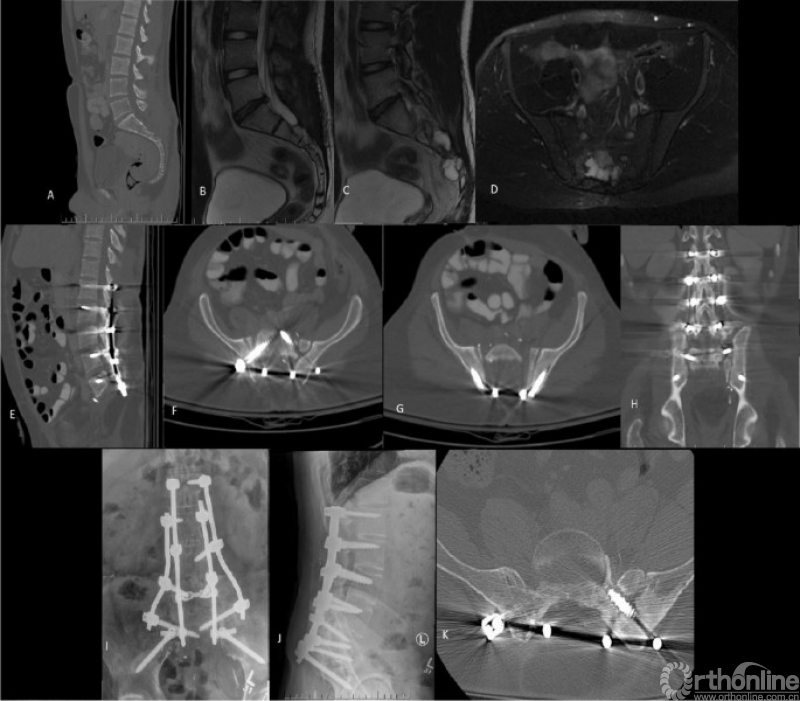

Ahmed Cherry等人发表的《Lumbopelvic shortening and local host bone-to-host bone reconstruction:a surgical method for lumbopelvic fusion following total sacrectomy》描述了全骶骨切除术后腰骶融合重建技术,用于治疗全骶骨切除术后的大骶骨缺损。